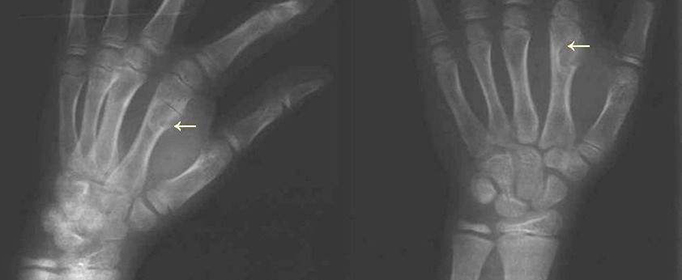

Ollier病又叫多发内生软骨瘤病,是一种少见的非遗传性良性肿瘤,由多数不对称分布在骨内的软骨病灶及骨膜下沉积所致。在机体的长短管状骨中、在肢体的单侧或双侧均可发病。因Ollier在1899年首次描述本病,故又称Ollier病。临床出现可触及的无痛性肿块,常侵及手或足,造成病残。本病有恶变的可能。

多发内生软骨瘤病是一种少见的非遗传性良性肿瘤,因Ollier在1899年首次描述本病,故又称Ollier病。临床出现可触及的无痛性肿块,常侵及手或足,造成病残。该病病因是多发内生软骨瘤病是骨骼发育过程中,由部分异位的骨骺板衍变而成。

多发内生软骨瘤病发病年龄在10岁以内,男性多于女性,在儿童时期出现症状,青春期出现明显畸形,以后逐渐稳定。临床表现为出现可触及的无痛性肿块,可侵及手或足,造成病残。病变侵及长管状骨,使内生软骨不能正常骨化,骨骺板不能正常生长,肢体出现短缩弯曲而畸形。如前臂向尺侧弯曲畸形、下肢膝外翻等。患者成年后肿瘤可停止生长。本病在成人可发生恶性变,恶变率为5%~25%。